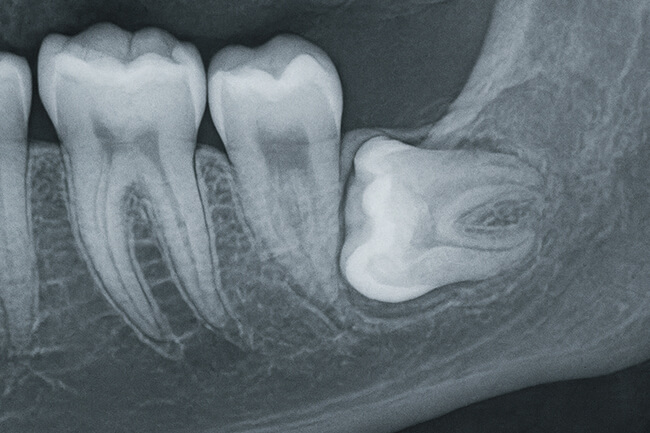

- 斜め・横向きに生える方

- 骨の中に埋まったままの方